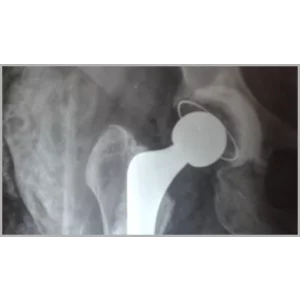

Right Total Hip Replacement And Right Total Knee Replacement In Single Stage Only

Categoryhip replacement surgery